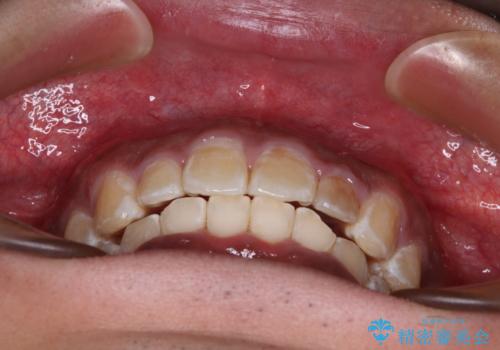

- 深く咬みこみ、前に飛び出した上顎前歯を気にして来院された患者様です。

口元の突出感はあまりありませんでしたが、上顎歯列が全体的に前方にあり、更には下顎歯列が深く咬みこんでいるために、上顎前歯が前方に突出している状態でした。

抜歯は行わず、補助装置を用いて上顎歯列全体を後方移動させ、ワイヤー装置にて奥歯の咬み合わせを改善していくこととしました。